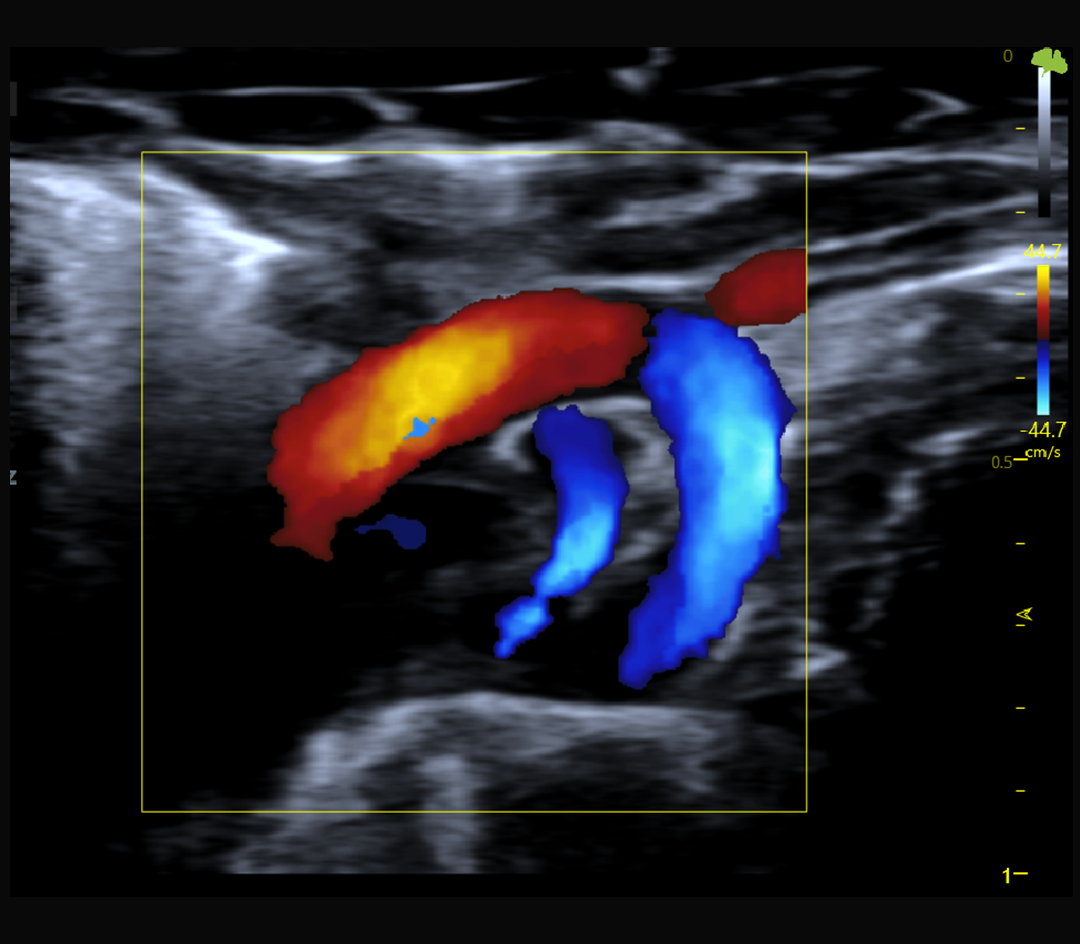

Hémodynamique et flux sanguins

Doppler couleur, pulsé et puissance

Doppler couleur, Doppler pulsé et Doppler puissance

Imagerie cardiaque haute cadence chez la souris et le rat